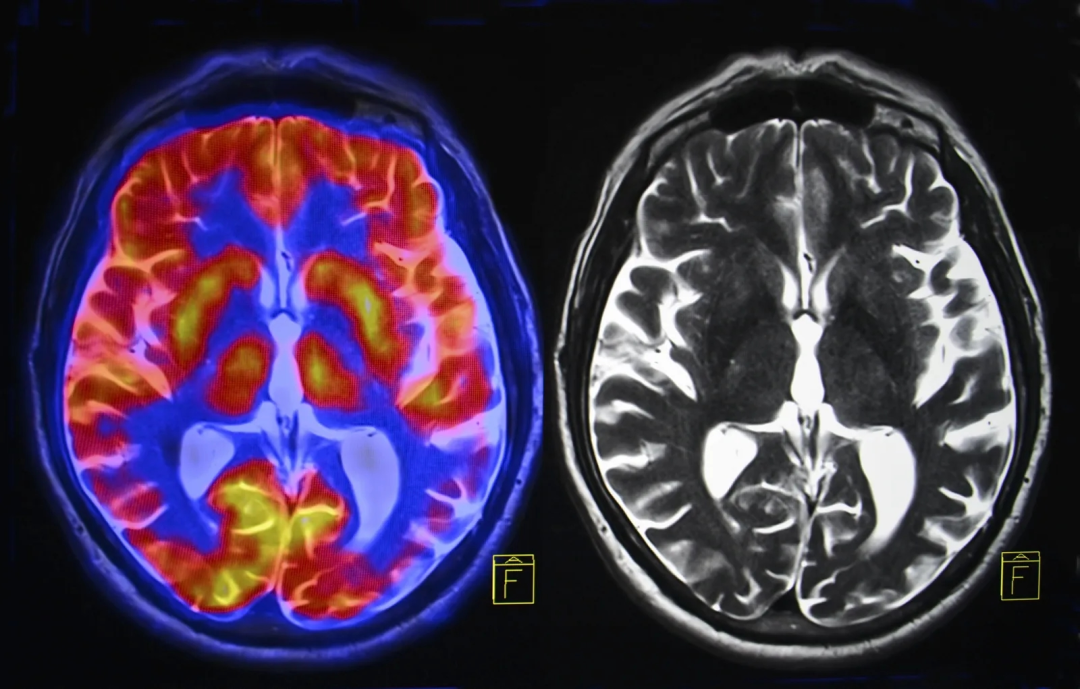

尽管人们对恐音症的影响了解甚多,但恐音症的病因却一直没被找到。现在,该大学的苏克宾德-库马尔(Sukhbinder Kumar)博士与伦敦大学学院惠康神经成像中心联合开展的一项研究,利用磁共振成像技术找到了其临床病因。研究结果表明,恐音症患者的大脑情绪控制机制--额叶和前岛叶皮层(AIC)之间--存在异常,导致他们对特定的噪音反应非常强烈。

Scans of brain activity from an MRI machineSEMNIC / ISTOCK

前岛叶皮层的功能是处理情绪和调节我们对各种刺激的反应。在测试过程中,恐音症患者的额叶和前岛叶皮层活动都有所增加,而非恐音症患者的前岛叶皮层活动有所增加,但额叶活动有所减少。研究人员推测,这可能表明这两个区域之间存在异常的控制机制,而连接模式的差异证明恐音症远非“令人讨厌的事”,而是一种真正的疾病。